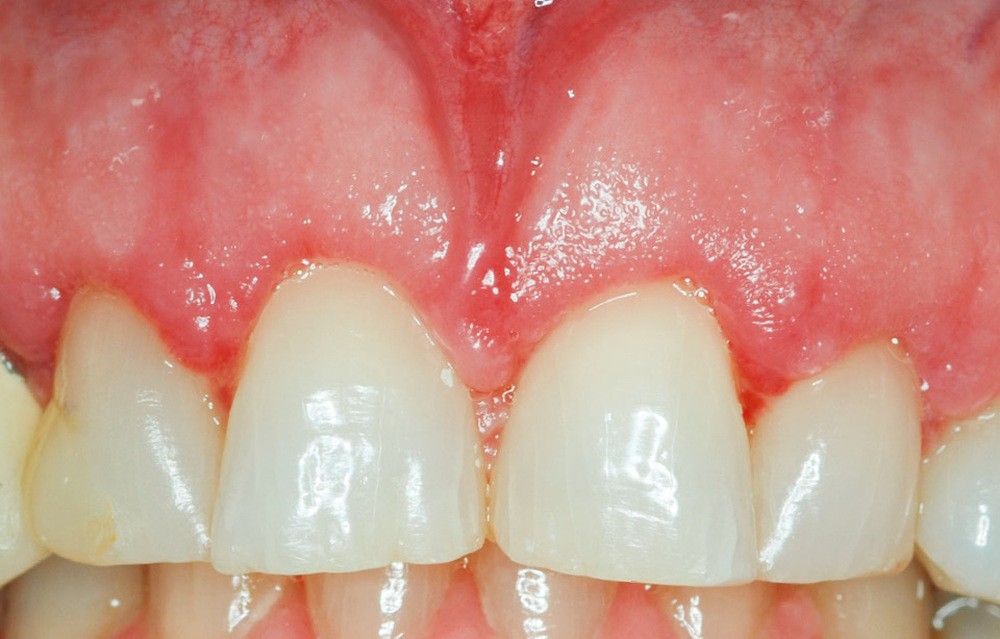

1 – Le système d’attache d’une dent est composé de l’os alvéolaire, du ligament alvéolo-dentaire et de l’attache épithélio-conjonctive ou attache supra-crestale. L’attache supra-crestale, anciennement confondue avec l’espace biologique, est un espace d’environ 2 mm [1] occupé par l’attache conjonctive (1 mm) et l’attache épithéliale (1 mm). Il est normalement visible à la radiographie rétro-alvéolaire entre le sommet de la crête osseuse et la jonction émail-cément. Comme une dent possède naturellement un sulcus, certains auteurs estiment qu’il convient d’y ajouter au moins 1 mm de sulcus libre de toute structure prothétique [2]. On peut donc considérer l’espace biologique comme un « espace clinique sanctuarisé » de 3 mm au sommet de la crête osseuse alvéolaire, nécessaire à la santé et à la stabilité parodontale. La violation de l’espace biologique génère un traumatisme parodontal aboutissant à des récessions gingivales ou des gingivites prothétiques (fig. 1a-b).

Même en l’absence de restauration, l’espace biologique n’est parfois naturellement pas correctement établi sur la dent. Ce phénomène est couramment décrit comme une éruption passive retardée. Elle peut être une indication d’élongation coronaire esthétique afin de rétablir la couronne clinique dans son intégralité (fig. 2a-c).